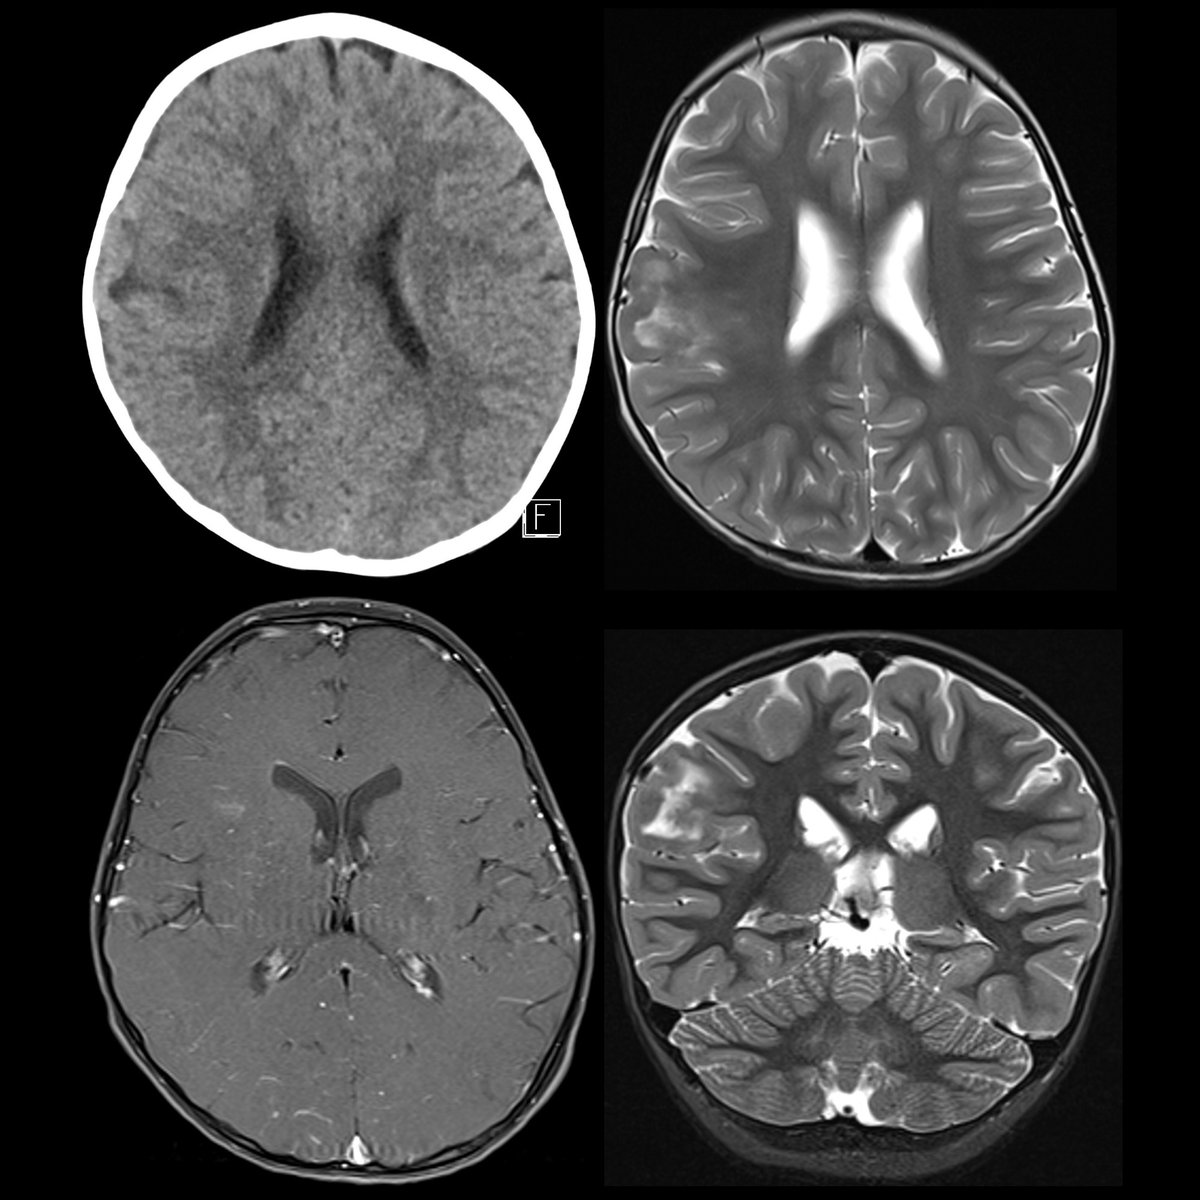

Preschooler with seizures CT without contrast(above left) shows right parietal ill-defined subcortical hypodensity. #FOAMed #FOAMPed #FOAMRad #PedsRad #RadEd #RadRes #EmergencyMedicine #FOAMem #NeuroRad #PediNeuroRad #NeuroRadiology #Neurology #Neurosurgery

Preschooler with seizures

CT without contrast(above left) shows right parietal ill-defined subcortical hypodensity.